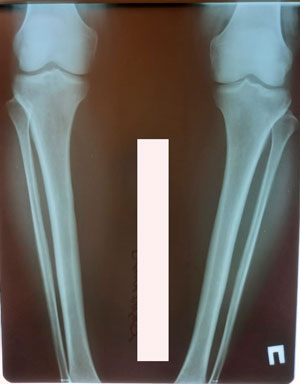

перед крутками

Вложения

image-22-12-20-04-38.jpeg